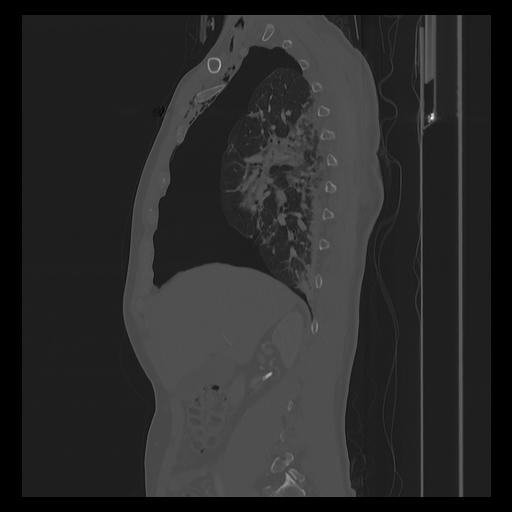

33 PULMON,CE,Sagittal,3.000,PULMON,Sagittal,